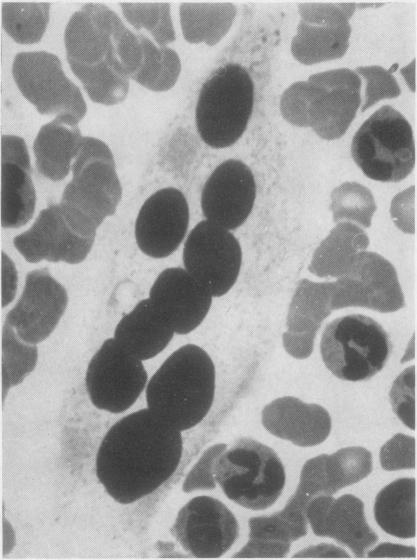

White-cell concentrates were made by a dextran sedimentation technique from the blood of 140 cases of malignant disease and 60 controls. The slides were searched for tumour cells and for other unusual cells with which they might be confused. Several million white cells were scanned in the slides from each case. Acceptable tumour cells were identified in the blood of seven patients, none of whom survived for more than a few months. These cells are illustrated, as well as various other cell types which may have been confused with malignant cells in the past. It is concluded that the cytology of white cell concentrates should be further explored before statistics about the occurrence of circulating tumour cells are accepted.

采用葡聚糖沉降技术从140例恶性疾病患者及60例对照者的血液中制备白细胞浓缩物。在玻片上查找肿瘤细胞以及可能与之混淆的其他异常细胞。对每个病例的玻片扫描数百万个白细胞。在7名患者的血液中鉴定出了可接受的肿瘤细胞,其中无一例存活超过几个月。文中展示了这些细胞以及过去可能与恶性细胞混淆的各种其他细胞类型。得出的结论是,在接受关于循环肿瘤细胞发生率的统计数据之前,应进一步探索白细胞浓缩物的细胞学。